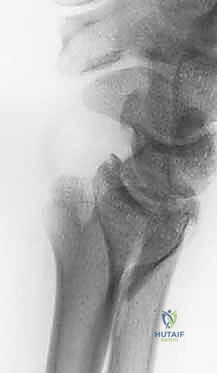

3. كسور الجزء الكردوسي الكردوسي (Ulnar Metaphyseal Fractures)

الجزء الكردوسي هو العنق أو المنطقة الانتقالية التي تربط رأس الزند بجسم العظم (Diaphysis).

هذه المنطقة تحتوي على عظم إسفنجي (Cancellous bone) وهي عرضة للكسور المفتتة (Comminuted fractures) خاصة عند كبار السن المصابين بهشاشة العظام، أو في حالات الحوادث عالية الطاقة. الكسر هنا يؤدي إلى قصر في طول عظم الزند، مما يغير من ميكانيكية توزيع الأحمال في المعصم ويسبب متلازمة انحشار الزند (Ulnar Impaction Syndrome).

توضيح لكسور الجزء الكردوسي الكردوسي

استخدام الأشعة السينية في التشخيص

1. الأشعة السينية (X-rays): بوضعيات متعددة (أمامية خلفية، وجانبية دقيقة). الوضعية الجانبية الحقيقية (True Lateral) حاسمة لاكتشاف أي خلع جزئي في المفصل (DRUJ).

2. الأشعة المقطعية ثلاثية الأبعاد (3D CT Scan): تُستخدم في الكسور المفتتة أو كسور رأس الزند المفصلية المعقدة، حيث تعطي خريطة دقيقة للجراح قبل الدخول لغرفة العمليات.